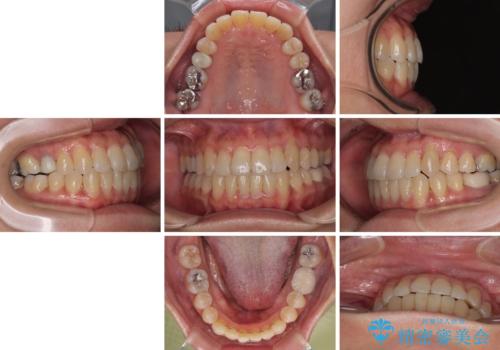

受け口と八重歯を改善 インビザライン矯正治療

受け口傾向の骨格であり、前歯はクロスバイトまたは切端咬合となっており、下顎を中心に歯列全体の後方移動を行い、IPR(歯と歯の間を削る)によってデコボコが解消するように設計し、インビザラインにより治療を行うこととしました。

受け口傾向のインビザライン矯正は比較的治療を行いやすいため、きれいに仕上げることができました。舌の突出癖が顕著であったため、改善のためのトレーニングをしっかりと行っていただきました。